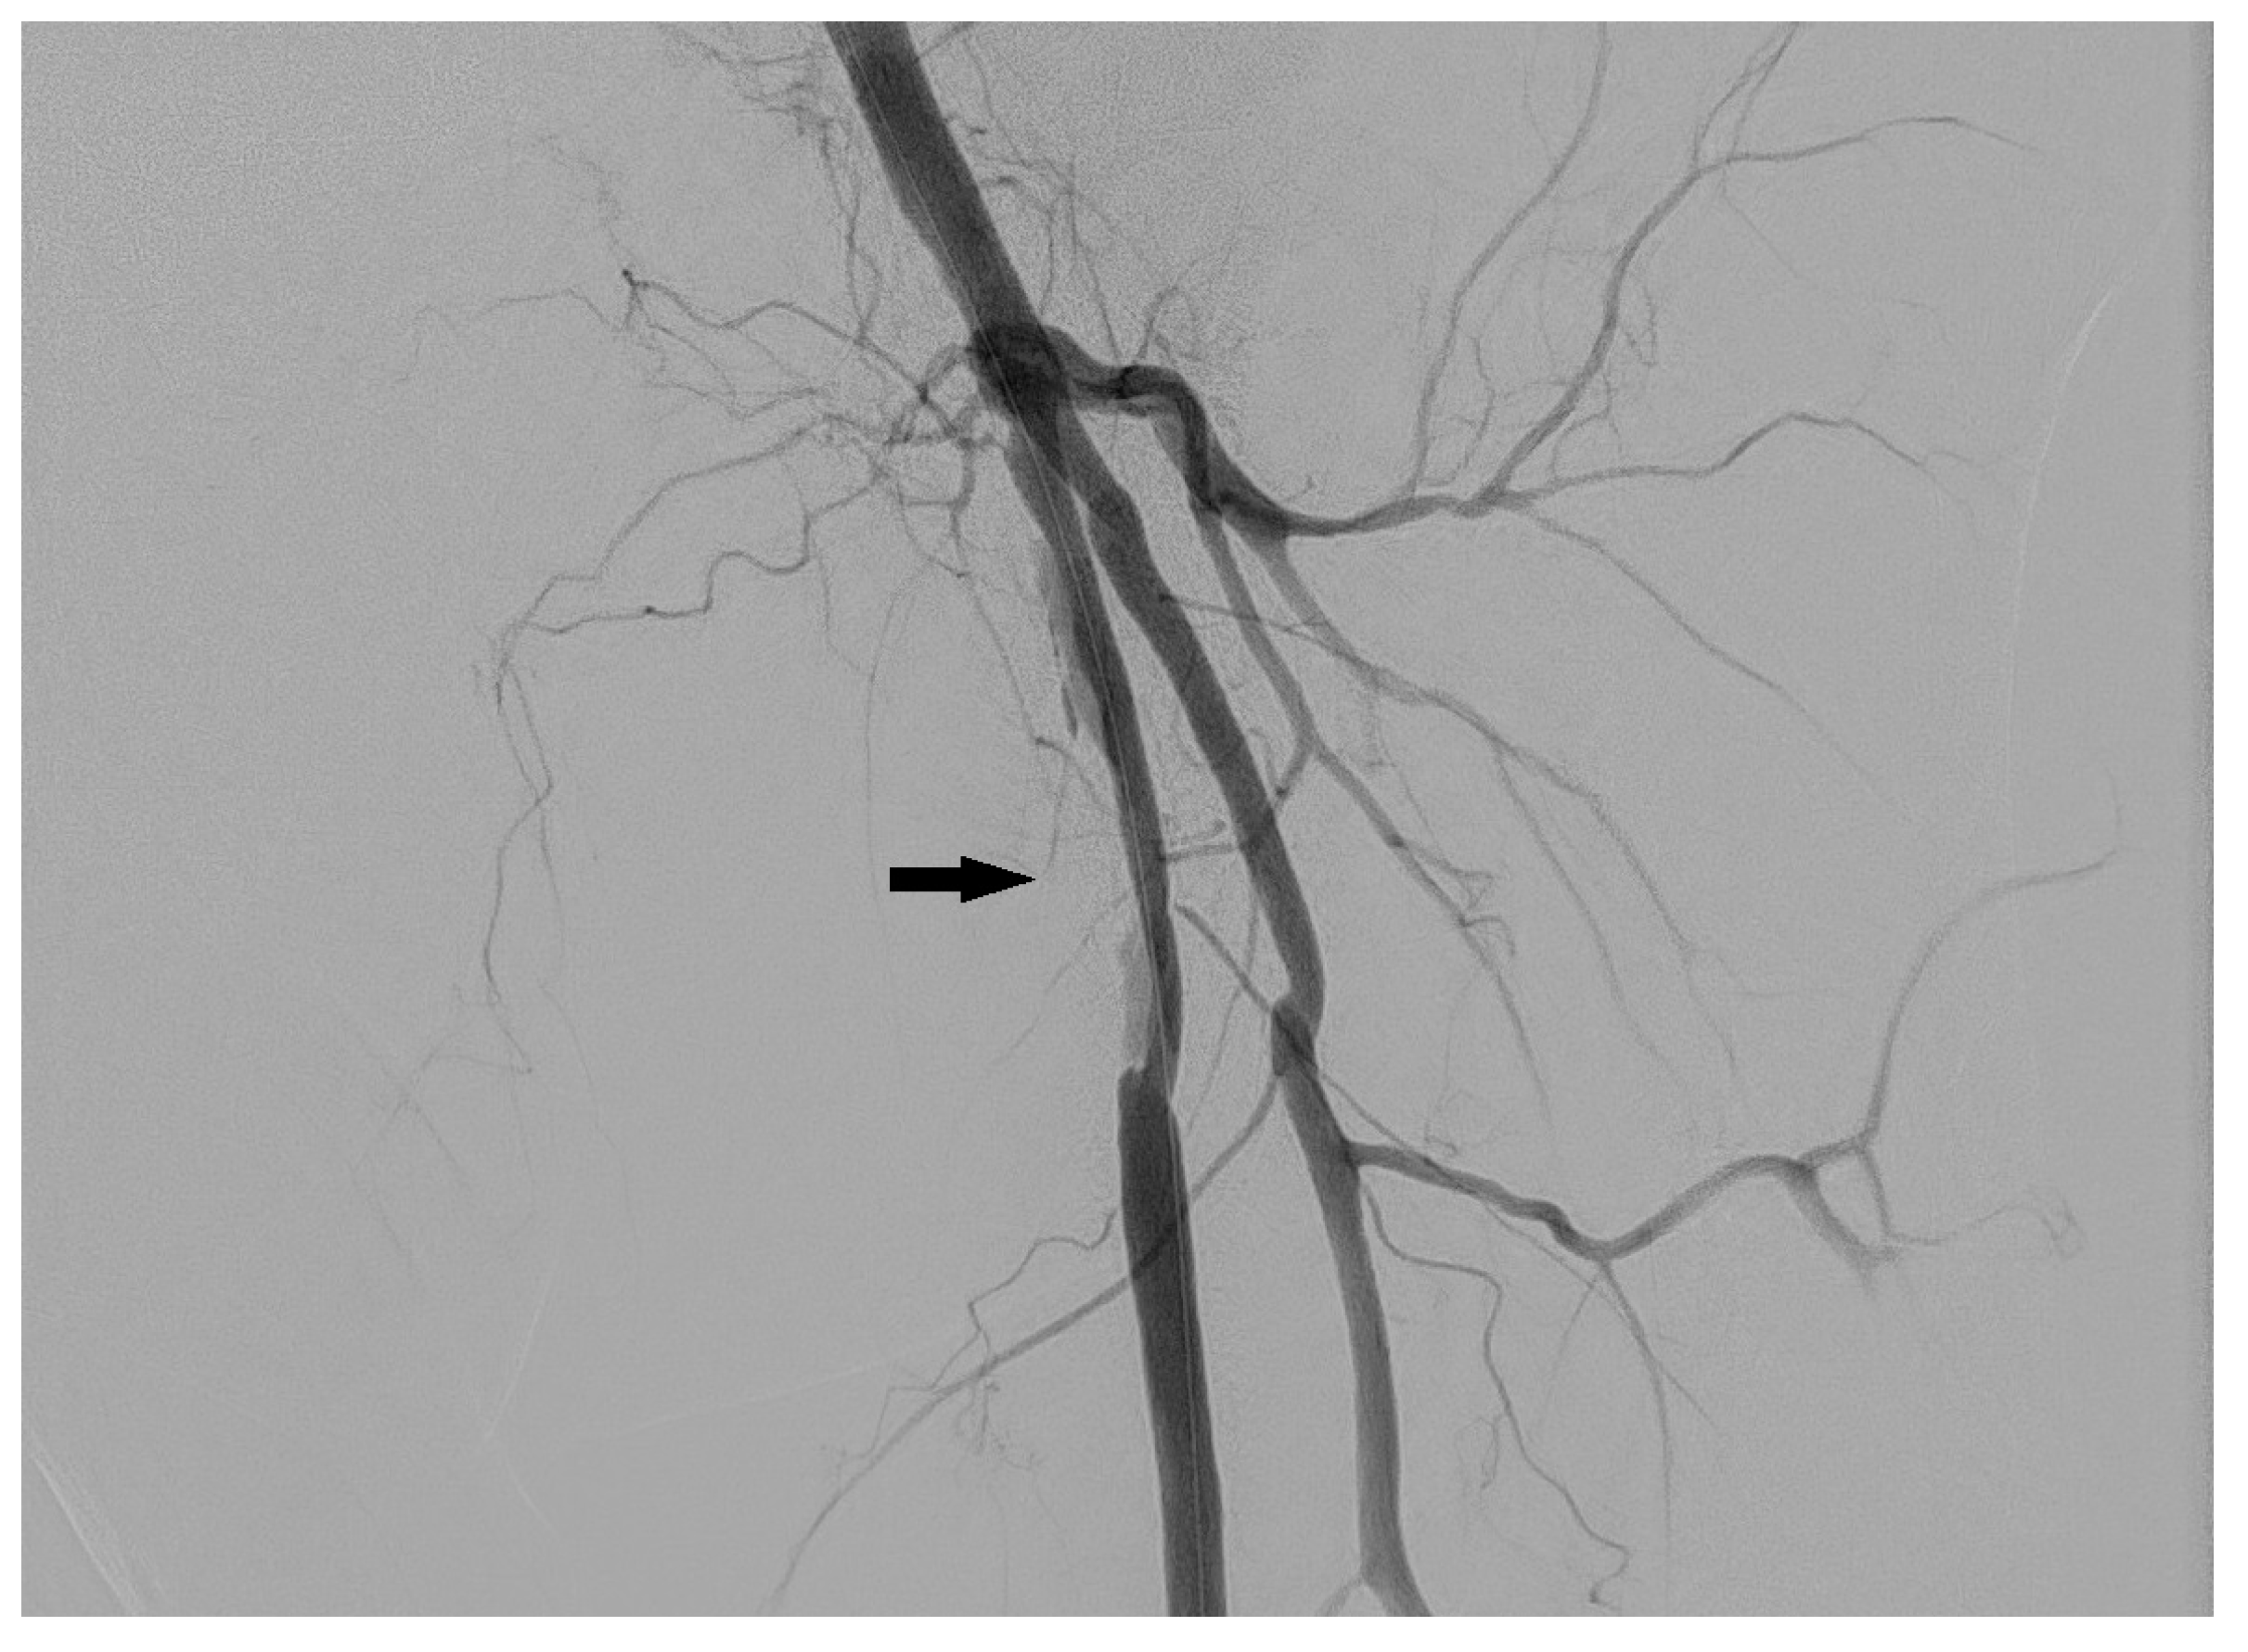

3.2. Dissection